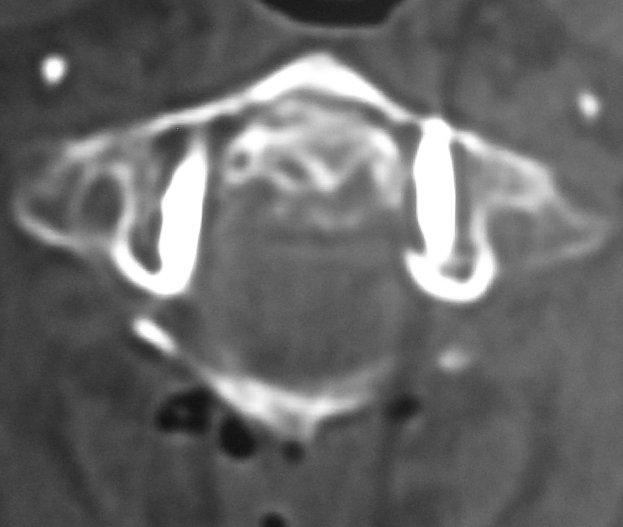

Koronal BT Kesiti - Os Odontoideum Aksiyal BT Kesiti - Atlas Füzyonu

Resim 3: Koronal BT kesidinde (sol) densin sklerotik kenarlarla ayrı bir kemik haline gelerek (=os odontoideum) C2 gövdesinden ayrışmış olduğu görülmektedir. Aksiyal BT kesidinde (sağ) os odontoideum'un atlas ön arkusuna kaynamış olduğu görülmektedir.